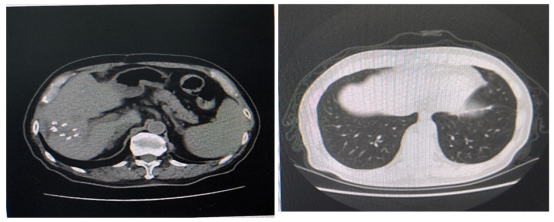

胸腹部增强CT(2021年04月26日):1.直肠中下段不规则增厚、强化,考虑直肠癌可能;2.肝后叶占位性病变考虑转移性肿瘤(范围约4.2×2.9cm)。

盆腔MRI(2021年04月26日):1.直肠管壁及周围改变,考虑中位直肠癌:T4aN2,CRM(阳性),EMVI(阳性)(图1)。

腹部MRI(2021年05月05日):1.肝右后叶下段(VI段)占位性病变,考虑转移(5×3.7cm)(图2)。

图1 2021年04月26日盆腔MRI

图2 2021年05月05日上腹部MRI